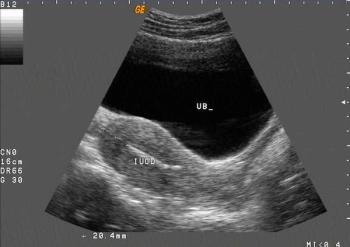

Gynecology Images: Normal Abnormal Obstetric Images: 1st Trimester: Normal Abnormal 2nd Trimester: Normal Abnormal 3rd Trimester: Normal Abnormal Medical Professionals: Upload Your Here Obstetric Images: 3rd Trimester: Normal Normal Thymus - Albana Cerekja Fetal urethra at 31 weeks: just before micturition - Albana Cerekja Normal Female: 4D still image - Effendi Mansoor Monolateral double renal artery,: Normal variant kidney artery supply - Albana Cerekja TRV Fetal Head: BPD and HC Measurements - SIEMENS Velamentosa insertion: 3rd trimester - Effendi Mansoor Umbilical Cord (3D Surface Rendering): Normal Cord - MEDISON SAG Fetal Face, Profile: Fetal Breathing on Color Doppler - SIEMENS 3D Surface Reconstruction: Face - Cayrol Guillermo 3D Surface Reconstruction: Extended Breech Presentation - Saied Mohamed Tohamy 3D Surface Reconstruction: Face - Juan Carlos Pons 3D Surface Reconstruction: Face and Foot - Cayrol Guillermo 3D Surface Reconstruction: Face - Juan Carlos Pons 3D Surface Reconstruction: Face - Juan Carlos Pons